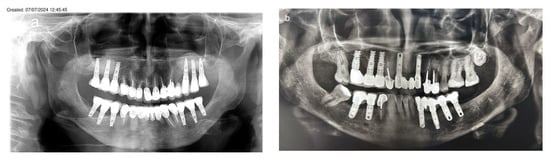

A 36-year-old woman was referred for bone augmentation and dental implant placement in the atrophic posterior mandibular ridges. The examination revealed partial edentulism of the mandible, with missing posterior teeth on both the right and left sides (Figure 6a). Computed tomography confirmed a significant horizontal bone deficit in the posterior mandibular regions bilaterally (Figure 6b,c). A two-stage treatment approach was planned. In the first stage, the honeycomb bone (HCT) technique was employed to augment the right and left posterior mandibular regions.

Figure 6.

(a) Bilateral posterior mandibular edentulism. (b,c) Computed tomography showing severe horizontal atrophy with knife-edge residual ridges. (d) The bone block harvested from the retromolar donor site. (e,f) The harvested bone block and its subsequent splitting, resulting in thin bone blocks and cortical wedges. (g) The bone augmentation procedure: grooves were created using high-speed at the recipient site, followed by the insertion and tapping of the cortical bone wedges into the grooves. (h,i) A thin bone plate is positioned over the bone wedges and secured with screws, creating bone compartments resembling a honeycomb. (j) Right side. (k) The bone compartments are filled with allogenic particulate bone graft to achieve the desired graft volume on the right side. (l,m) Double-layer, tension-free closure of the recipient sites performed using BFFGs. (n–q) CBCT scan, four months postoperatively show significant bilateral horizontal bone gain. (r) Two implants were placed on the right side and four implants on the left side. (s) Panoramic view at 8-year follow-up. (t–v) CBCT scans taken 10 years after implant placement reveal stable augmented bone levels. (w) Eleven-year follow-up periapical x-ray of the left side, demonstrating no significant marginal bone loss. (x) 3 mm of marginal bone loss observed at the mesial implant. The yellow arrows show the cortical wedges that remain visible at the recipient sites.

In May 2013, a cortical bone block was harvested from the right retromolar area (Figure 6d). The harvested block was then split, yielding two thin bone blocks and multiple bone wedges (Figure 6e,f). The recipient sites were prepared by creating grooves, into which the bone wedges were inserted in a stable position bilaterally (Figure 6g). Two thin bone blocks were then secured over the bone wedges using screws. This configuration resulted in multiple bone compartments resembling a honeycomb structure (Figure 6h–j). After trimming any sharp edges, the compartments were filled with particulate allograft bone substitute, achieving the desired final bone volume (Figure 6k). The augmented sites were then covered with a resorbable membrane and a free buccal fat pad graft (BFFG) before being closed in a tension-free manner (Figure 6l,m). The healing process was uneventful throughout the follow-up period. A CBCT scan performed four months postoperatively, in September 2013, confirmed significant horizontal bone gain of 4–6 mm (Figure 6n–q). Upon reentry under local anesthesia, the newly formed bone volume was evident, with the bone wedges fully integrated into the regenerated bone mass. Six dental implants were successfully placed (Figure 6r). After three months, all the implants had achieved full osseointegration, allowing for final prosthetic rehabilitation. This case has been followed for 11 years. A panorex obtained at 8 years showed implants without marginal bone loss (Figure 6s), and a CBCT scan obtained in September 2023 demonstrated stable bone volume 10 years post-surgery, with no resorption of the augmented bone blocks (Figure 6t–v). Periapical radiographs taken in July 2024 further confirmed the long-term stability of the outcomes and implant survival. At this time, the first implant on the right side showed a 3mm marginal bone loss, possibly due to food impaction from a decayed adjacent premolar. The remaining five implants exhibited no signs of marginal bone loss. The cortical wedges remained visible at the recipient sites in both figures (Figure 6w,x).